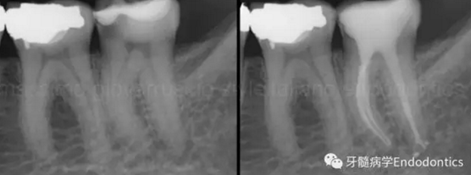

圖1.探查冠方2/3可以獲得有關根管系統(tǒng)解剖形態(tài)的相關信息,獲得根管彎曲和多重彎曲程度,或者是否存在根管彎曲的一些重要反饋。醫(yī)生需要重視五種可能遇到的根管解剖類型(包括融合、彎曲、多重彎曲、分歧、分支)。

當建立直線通路、找到所有的根管口后,重心應轉移到根管預備上。若牙髓存在活力且持續(xù)滲血,應使髓室內充滿粘性螯合劑。在牙髓已壞死的情況下,應使用加熱的5.25%次氯酸鈉溶液沖洗并徹底充滿髓室。探查前,根據術前X線片測量并預彎小的不銹鋼銼,以順應預估的根管長度及彎曲度。使用0.02錐度的10號不銹鋼手用K銼探查根管冠方2/3。